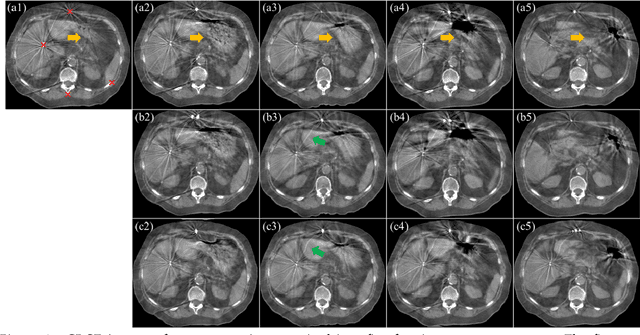

Abstract:This paper aims to create a deep learning framework that can estimate the deformation vector field (DVF) for directly registering abdominal MRI-CT images. The proposed method assumed a diffeomorphic deformation. By using topology-preserved deformation features extracted from the probabilistic diffeomorphic registration model, abdominal motion can be accurately obtained and utilized for DVF estimation. The model integrated Swin transformers, which have demonstrated superior performance in motion tracking, into the convolutional neural network (CNN) for deformation feature extraction. The model was optimized using a cross-modality image similarity loss and a surface matching loss. To compute the image loss, a modality-independent neighborhood descriptor (MIND) was used between the deformed MRI and CT images. The surface matching loss was determined by measuring the distance between the warped coordinates of the surfaces of contoured structures on the MRI and CT images. The deformed MRI image was assessed against the CT image using the target registration error (TRE), Dice similarity coefficient (DSC), and mean surface distance (MSD) between the deformed contours of the MRI image and manual contours of the CT image. When compared to only rigid registration, DIR with the proposed method resulted in an increase of the mean DSC values of the liver and portal vein from 0.850 and 0.628 to 0.903 and 0.763, a decrease of the mean MSD of the liver from 7.216 mm to 3.232 mm, and a decrease of the TRE from 26.238 mm to 8.492 mm. The proposed deformable image registration method based on a diffeomorphic transformer provides an effective and efficient way to generate an accurate DVF from an MRI-CT image pair of the abdomen. It could be utilized in the current treatment planning workflow for liver radiotherapy.